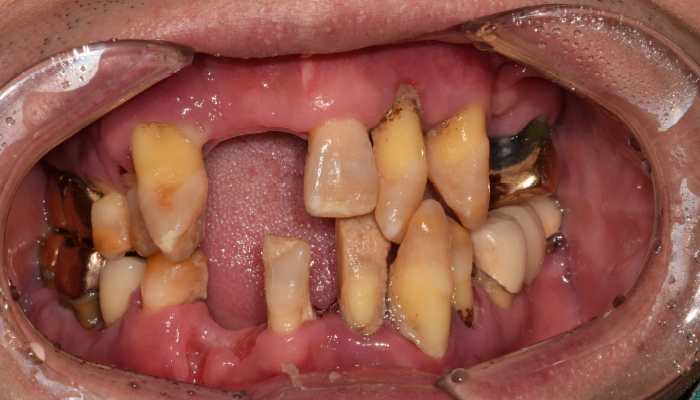

틀니 임플란트 전후 사례

• 식립전

식립후